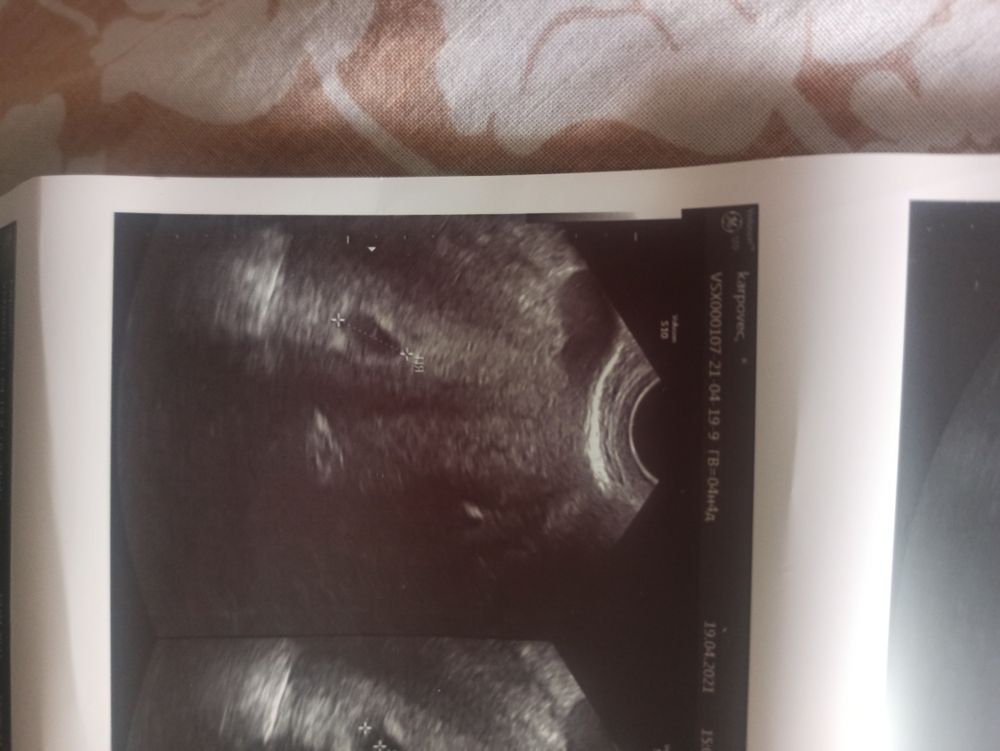

Плодное яйцо визуализируется в полости матки, всё хорошо 😊😊

Правда сообщили, что у меня варикоз вен малого таза, расширение до 7мм. У меня и на ногах немного видно вены. Необходимо будет сходить к флебологу на консультацию. Кто сталкивался с этим, как лечили?

И ещё вопрос. В заключении УЗИ написали, что в левом яичнике визуализируется 1 фолликул. Что это значит? Забеременела я с правого яичника, жёлтое тело сейчас в нём. А фолликул в левом. Помогите, любопытство одолевает 🙏🏻😊